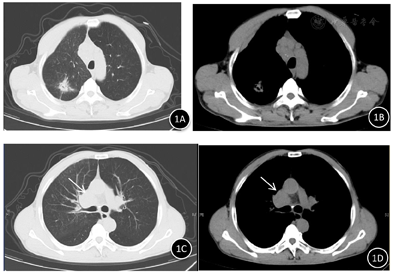

胸部CT、PET-CT、气管镜检查及病理结果(图1,图2,图3,图4,图5,图6)。

患者中年男性,慢性病程,主要表现为咳嗽、咳痰、咯血,查体右锁骨上可触及多个肿大淋巴结,质硬,固定,长期大量吸烟史,proGRP、NSE、CEA明显升高,胸部CT示右肺上叶不规则团块影,边缘分叶,多发毛刺,纵隔及右侧肺门可见多发肿大淋巴结。根据左肺下叶背段支气管黏膜活检为鳞状细胞癌,右肺上叶肺活检为肺腺癌,颈部淋巴结活检为小细胞肺癌。故本例患者肺癌诊断明确,为同时性多原发肺癌。鳞癌是在气管镜下发现,为早期阶段。腺癌的体积比较大,小细胞肺癌原发灶考虑为右侧肺门附近,如图1C、图1D、图2B中白色箭头所示,锁骨上淋巴结穿刺病理证实为小细胞肺癌转移,故在肿瘤标志物上proGRP、CEA明显升高,SCC正常,也符合其临床情况,最终分期:cT2N3M1c,Ⅳb期。